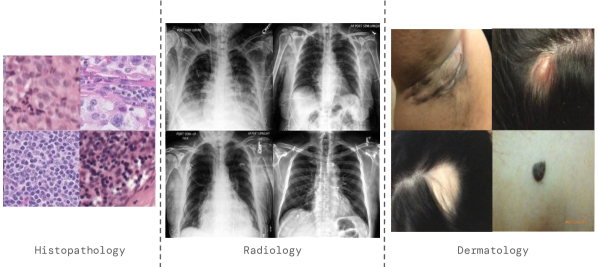

Prior work has shown that a developed model may perform unexpectedly poorly on underrepresented populations or population subgroups in radiology (Larrazabal et al., 2020; Seyyed-Kalantari et al., 2021), histopathology (Yu et al., 2018) and dermatology (Abbasi-Sureshjani et al., 2020). However, the issues of robustness to distribution shifts and statistical fairness have rarely been tackled together. In this work, we leverage generative models and potentially available unlabelled data to capture the underlying data distribution and augment real samples when training diagnostic models across these three modalities. We show that combining synthetic and real data can lead to significant improvements in top-level performance, while closing the fairness gap with respect to different sensitive attributes under distribution shifts111We borrow the term sensitive attribute from the fairness literature to describe demographic attributes we want the model to be fair against. All of the data used in this research was de-identified before DeepMind and Google gained access to it.. Finally, we show that diffusion models are able to generate high quality images (see Figure 1) across modalities and perform an in-depth analysis to shed light on the mechanisms that improve generalization capabilities of the downstream classifiers.

Refer to caption

Figure 1: Samples generated by our conditional diffusion model for different imaging modalities.